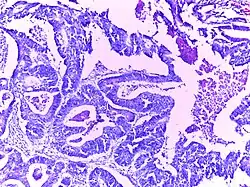

![]() | Bronchoalveolar carcinoma | Lepidic pattern of growth of tumor cells along the alveolar wall resembling butterfly sitting on fence. Normal alveoli is seen towards right side. | Category: Histopathology of bronchio-alveolar carcinoma | Bronchio-alveolar carcinoma |